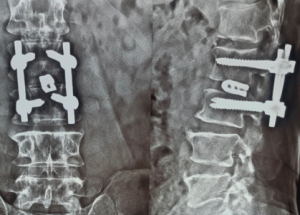

Expert spine services including minimally invasive surgery, pain management, and deformity correction.